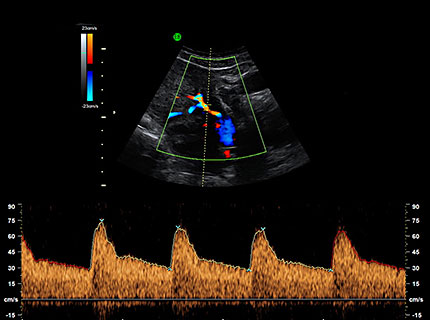

Zentraler Bestandteil ist die differenzierte Ultraschalluntersuchung: Hierbei werden die fetale Entwicklung und die Organe beurteilt sowie die Nackentransparenz gemessen. Ergänzend kann gegebenenfalls eine Laboruntersuchung der Plazentahormone (PAPP-A, freies beta-HCG) im mütterlichen Blut sinnvoll sein.

Als „Nackentransparenz“ wird ein Flüssigkeitsraum unter der Haut des Nackens bezeichnet. Dieser lässt sich im ersten Trimenon mittels hoch auflösenden Ultraschalls messen. Kinder mit chromosomalen Auffälligkeiten haben oft zwischen der 12. und der 14. Schwangerschaftswoche einen deutlich größeren Flüssigkeitsraum – also eine höhere Nackentransparenz – als gesunde Kinder. Zudem kann eine erhöhte Nackentransparenz ein Hinweis auf eine andere Erkrankung oder Fehlentwicklung (z. B. Herzfehler > fetale Echokardiographie) sein. Aber auch gesunde Kinder können eine verbreiterte Nackentransparenz haben.

Gegebenenfalls bietet sich zusätzlich zur Messung der Nackentransparenz und der differenzierten Organdiagnostik eine Blutuntersuchung an, wodurch sich die Aussagekraft erhöht. Hierbei werden die Konzentrationen eines Schwangerschaftshormons (freies beta-HCG) sowie eines spezifischen Schwangerschaftsenzyms (PAPP-A) im mütterlichen Blut bestimmt, die bei chromosomalen Erkrankungen besondere Konstellationen haben können. In Kombination mit dem mütterlichen Alter, dem Schwangerschaftsalter und der Beurteilung von zusätzlichen Ultraschallmerkmalen (etwa des Nasenbeins und der kindlichen Blutflussmuster) lässt sich so für jede Frau die individuelle Wahrscheinlichkeit für die häufigsten Chromosomenfehler ermitteln. Die Risikoberechnung erfolgt nach den Kriterien und statistischen Grundlagen der Fetal Medicine Foundation London.